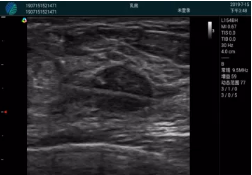

清晰顯示腺體內(nèi)低回聲快影,邊界清晰,包膜較光滑

確定進針路徑并實時監(jiān)測抽吸針與腫塊位置關(guān)系

抽吸針進入腫塊內(nèi)部進行旋切

抽吸過程中可見腫塊明顯縮小,并根據(jù)腫塊位置改變針道位置

抽吸旋切后再進行超聲復(fù)查,原腫塊區(qū)域未見殘留組織及出血